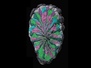

When searching for new treatments and tactics to stave off disease, it's just as important to know what doesn’t work as to understand what does. Alzheimer’s disease is caused in part by an over accumulation of a protein called tau in neurons (brain cells). Tau is essential for healthy brain cell function, but too much causes problems. Previous research had implied that a particular molecule, MAPT-AS1, might help keep tau levels under control. A new study confirmed that it is present in neurons, but found evidence that it does not affect tau. When MAPT-AS1 was over-expressed (red in the neurons pictured), tau (brown) levels stayed the same. This suggests we can cross MAPT-AS1 off the list of potential treatment approaches, which is one important step in narrowing down the search.